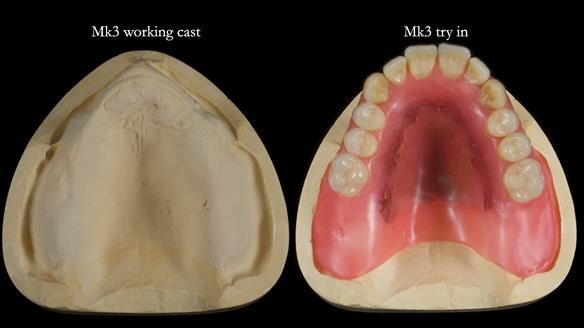

Twelve months after the final extractions, I made the Mk3 definitive complete upper denture.

Three months after fitting, a reline was carried out to adapt to tissue changes from the canine and molar extractions.

For the Mk3, we embedded the metal base fully within the fitting surface acrylic. This design allowed adjustment of the polished surface using universal marking spray to fine-tune sibilance and prevented any join between the metal and acrylic from being felt by the tongue.